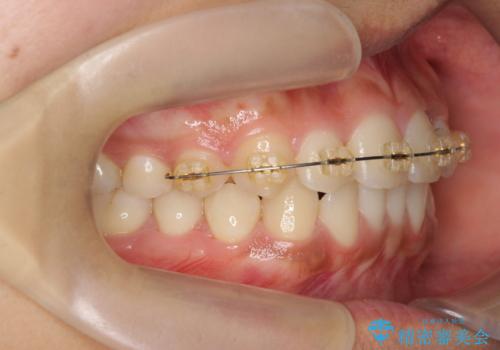

- 前歯のガタつき、上下たがい違いになっている歯並び(クロスバイト)の改善を求めて来院されました。

インビザラインによる矯正治療を行いますが、クロスバイトの改善をワイヤー部分矯正で事前に行うことにより治療期間の短縮する治療計画を立案します。

上下すれ違った噛み合わせはマウスピースでは改善に時間がかかり、またねじれが残ってしまうことも多々見られます。

マウスピース矯正を行う前に、これらの症状の改善の得意なワイヤー部分矯正を行うことで治療期間を短縮し、確実にすれ違いを改善することができます。